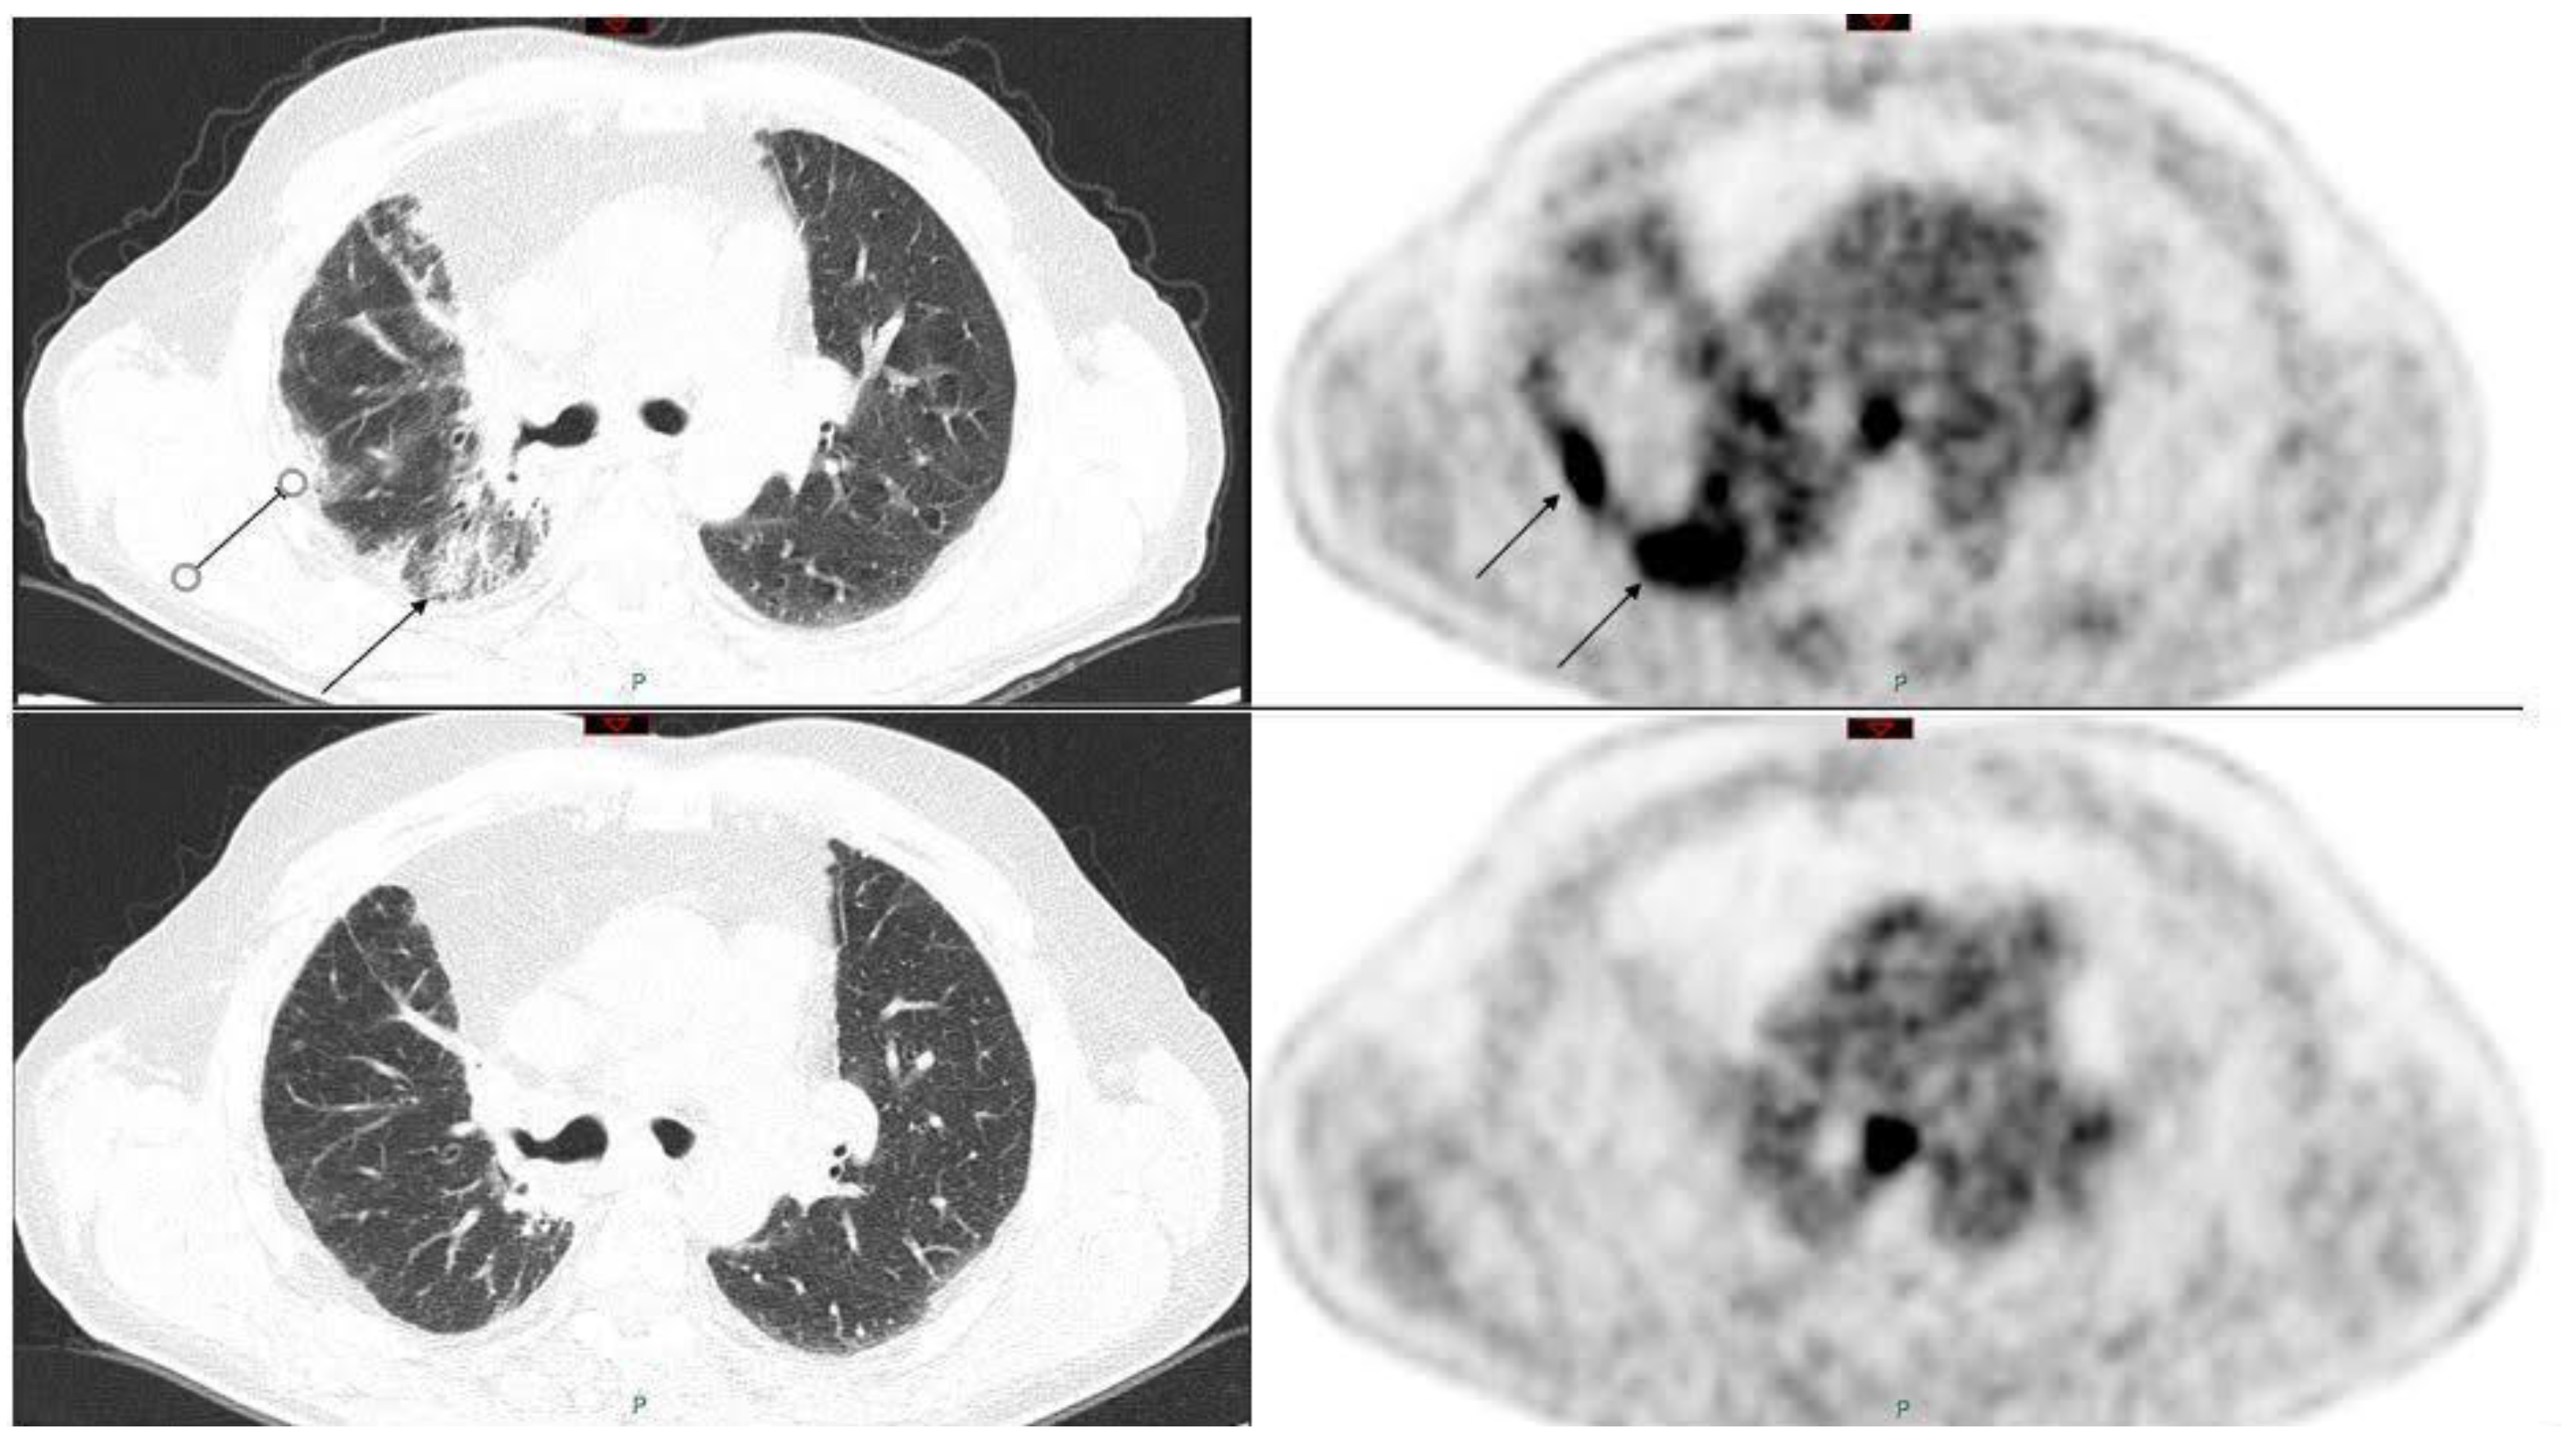

- Buchler, T.; Bomanji, J.; Lee, S.M. FDG-PET in bleomycin-induced pneumonitis following ABVD chemotherapy for Hodgkin’s disease—A useful tool for monitoring pulmonary toxicity and disease activity. Haematologica 2007, 92, e120-1. [Google Scholar] [CrossRef]

- Basu, S.; Saboury, B.; Werner, T.; Alavi, A. Clinical utility of FDG-PET and PET/CT in non-malignant thoracic disorders. Mol. Imaging Biol. 2011, 13, 1051–1060. [Google Scholar] [CrossRef]

- Razzouk-Cadet, M.; Picard, A.; Grangeon-Chapon, C.; Lacour, J.P.; Montaudié, H. Nivolumab-Induced Pneumonitis in Patient with Metastatic Melanoma Showing Complete Remission on 18F-FDG PET/CT. Clin. Nucl. Med. 2019, 44, 806–807. [Google Scholar] [CrossRef]